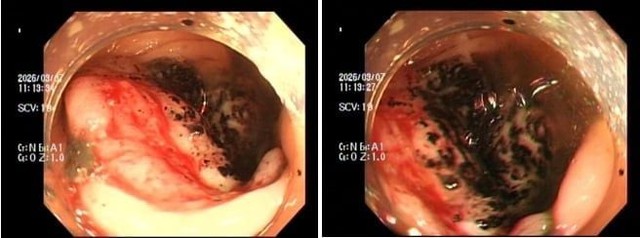

Chị P.V.P.U (SN 1991) đến khám chỉ vì... ông xã thấy dạo này da dẻ chị quá xanh xao. Bản thân chị thỉnh thoảng cũng cảm thấy đau bụng nhẹ, thoáng qua nhưng lại tặc lưỡi bỏ qua vì nghĩ là rối loạn tiêu hóa thông thường. Khi thăm khám, bác sĩ phát hiện chị bị thiếu máu nặng. Ngay lập tức, chị được chỉ định nội soi đại tràng, kết quả khiến cả hai vợ chồng sững sờ: Có một khối u lớn ở đại tràng phải, bề mặt loét và rất dễ chảy máu, kết quả mô học khẳng định: Ung thư đại trực tràng.

Khối u đại tràng (đặc biệt là đại tràng phải) thường không gây tắc ruột ngay mà có bề mặt dễ viêm loét. Chúng tựa như những "kẻ cắp", mỗi ngày làm chảy một lượng máu rất nhỏ lẫn vào phân mà mắt thường khó nhận ra (máu ẩn trong phân).

Hình ảnh ung thư đại trực tràng. Ảnh: BVCC